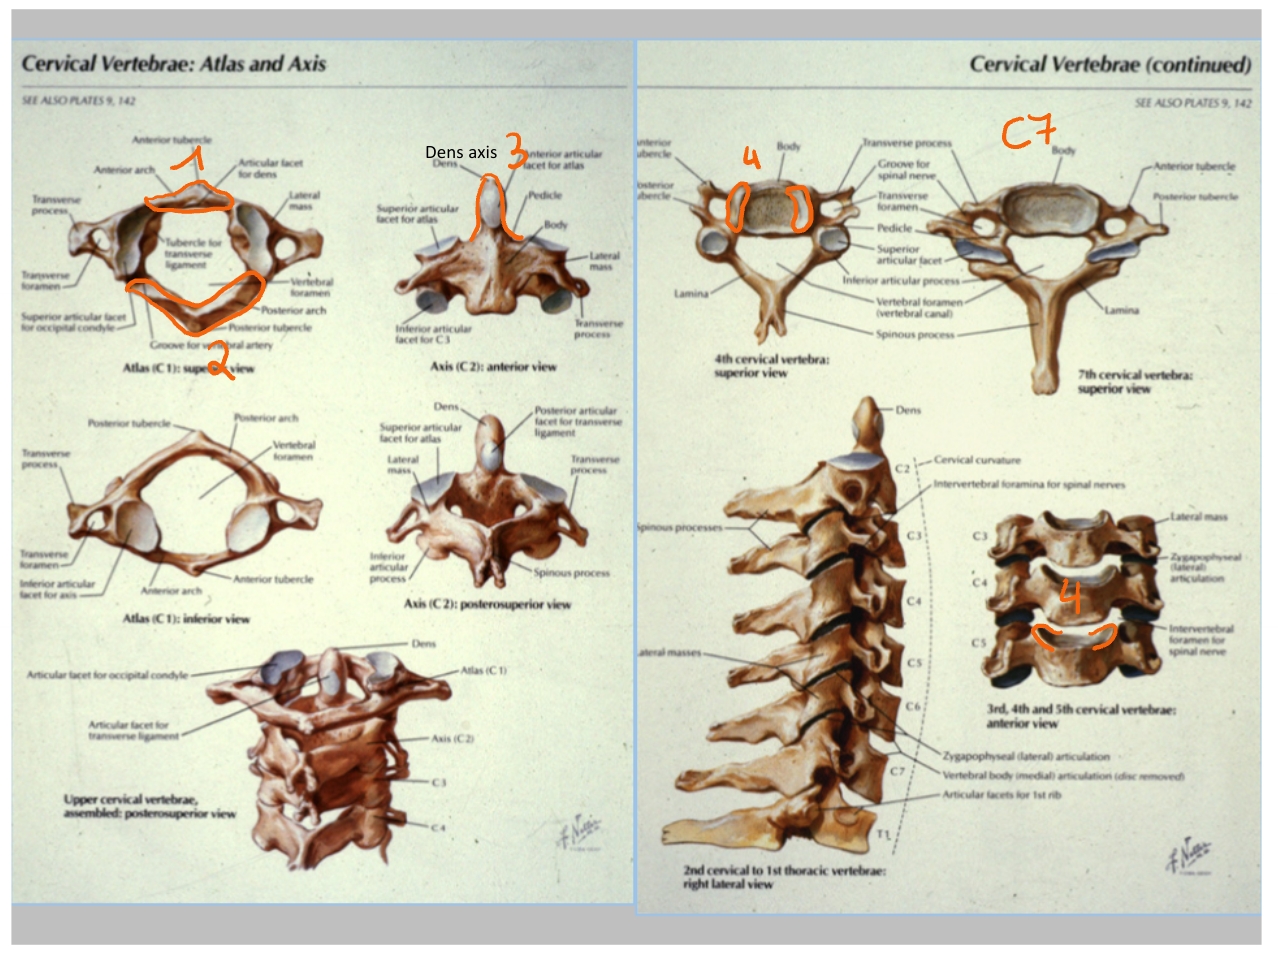

arcus anterior

arcus posterior

dens axis

processus uncinatus

corpus C4

processus uncinatus

processus spinosus C6

processus spinosus C7

corpus T1

processus transversus T1

→ T1: beste referentie => heeft grote processi transversi